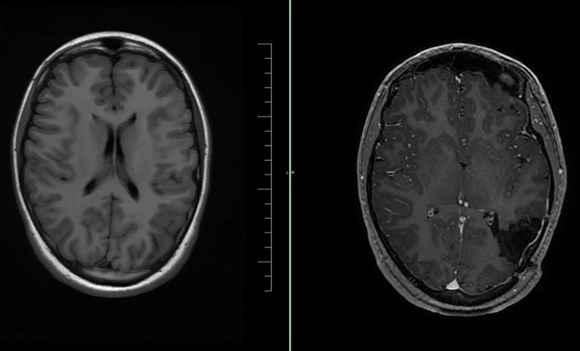

Nová šance na trvalé odstranění záchvatů